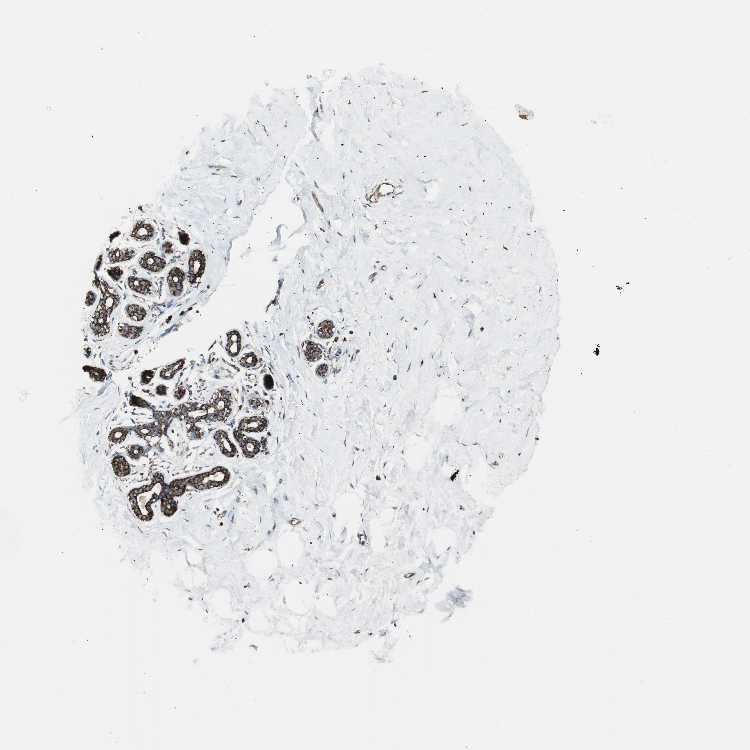

BREAST - Antibody stainingi

Antibody staining in the annotated cell types in the current human tissue is reported as not detected, low, medium, or high, based on conventional immunohistochemistry profiling in selected tissues. This score is based on the combination of the staining intensity and fraction of stained cells.

Each image is clickable and will lead to virtual microscopy that enables deeper exploration of all samples and also displays staining intensity scores, fraction scores and subcellular localization as well as patient and tissue information for each sample.

Antibody HPA003037

Adipocytes Medium

Glandular cells High

Myoepithelial cells High